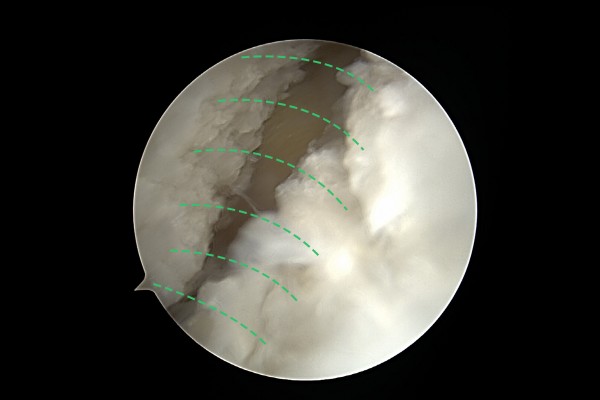

관절내시경 화면에서 족저근막이 확인됩니다.

96707d45bfa78bc815f4e3f85a28a525_1757924051_5889.jpg

족저근막을 수술도구를 이용하여 부분적으로 터서 늘려줍니다.

96707d45bfa78bc815f4e3f85a28a525_1757924062_0251.jpg

시간이 지나면 자연스럽게 연결되어 족저근막이 늘어나는 효과를 얻게 됩니다.